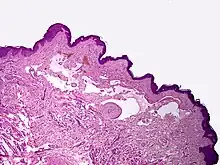

Proliferating lymphangioma, H&E stain. Sometimes endothelial cells begin to divide excessively.

Microscopically, the vesicles in lymphangioma circumscriptum are greatly dilated lymph channels that cause the papillary dermis to expand. They may be associated with acanthosis and hyperkeratosis. There are many channels in the upper dermis which often extend to the subcutis (the deeper layer of the dermis, containing mostly fat and connective tissue). The deeper vessels have large calibers with thick walls which contain smooth muscle. The lumen is filled with lymphatic fluid, but often contains red blood cells, lymphocytes, macrophages, and neutrophils. The channels are lined with flat endothelial cells. The interstitium has many lymphoid cells and shows evidence of fibroplasia (the formation of fibrous tissue). Nodules (A small mass of tissue or aggregation of cells) in cavernous lymphangioma are large, irregular channels in the reticular dermis and subcutaneous tissue that are lined by a single layer of endothelial cells. Also an incomplete layer of smooth muscle also lines the walls of these channels. The stroma consists of loose connective tissue with a lot of inflammatory cells. These tumors usually penetrate muscle. Cystic hygroma is indistinguishable from cavernous lymphangiomas on histology.[4]